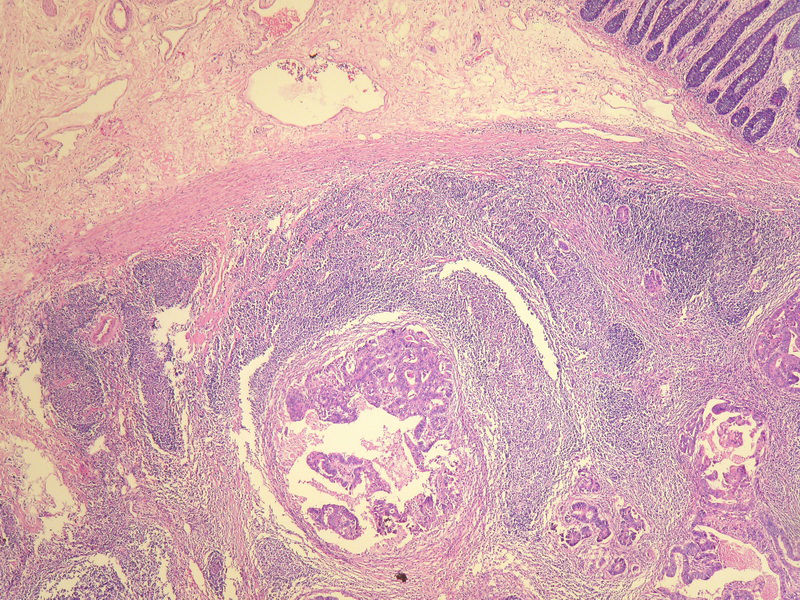

70岁男性,乙状结肠息肉样肿物。

请教:这个乙状结肠肿瘤侵犯到哪一层??图1

×参考诊断

粘膜下层

仅就浸润的深度而言,粘膜下层应该没什么争议。但是肿瘤表面的粘膜腺体是很好的,从低倍图看,不能排除是个转移灶的可能。请临床再查一查除了这个以外别的部位还有没有肿块。

浸润深度为粘膜下层,可粘膜表面的腺体完整,同意楼上的观点。谢谢